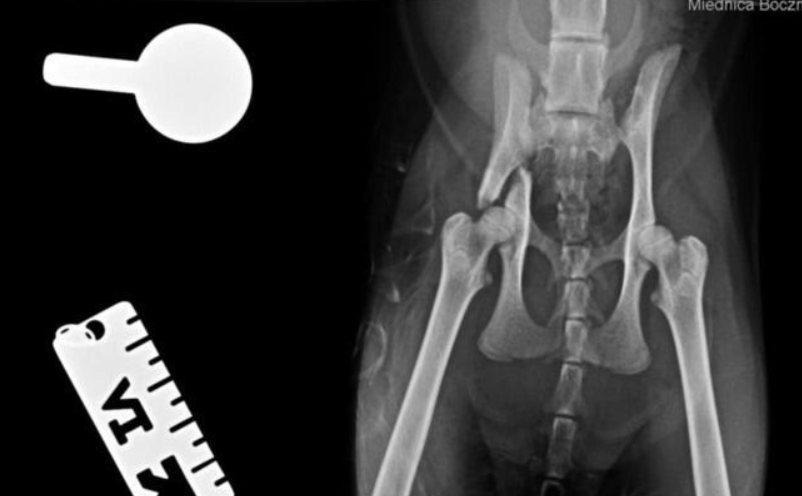

Kotka została znaleziona pod blokiem przez cudowną osobę, która nie pozostała obojętna i natychmiast powiadomiła odpowiednie służby! W wyniku upadku Felcia odniosła bardzo poważne obrażenia: przesunięcie kręgów w odcinku krzyżowym kręgosłupa, złamanie miednicy i zwichnięcie stawu biodrowego. Na szczęście zachowała czucie, więc mamy wielką nadzieję na powrót małej do pełnej sprawności, do czego długa droga...

Kicia jest już pod opieką naszej fundacji! Jest już po skomplikowanej operacji, której podjął się znakomity ortopeda, doktor Kacper Weigel. Z całego serca dziękujemy Panu doktorowi oraz całemu zespołowi Kliniki Weterynaryjnej Puławska za błyskawiczną pomoc i zaangażowanie! Wszystko się udało i po 6 tygodniowym unieruchomieniu w kennelu rozpoczniemy rehabilitację.